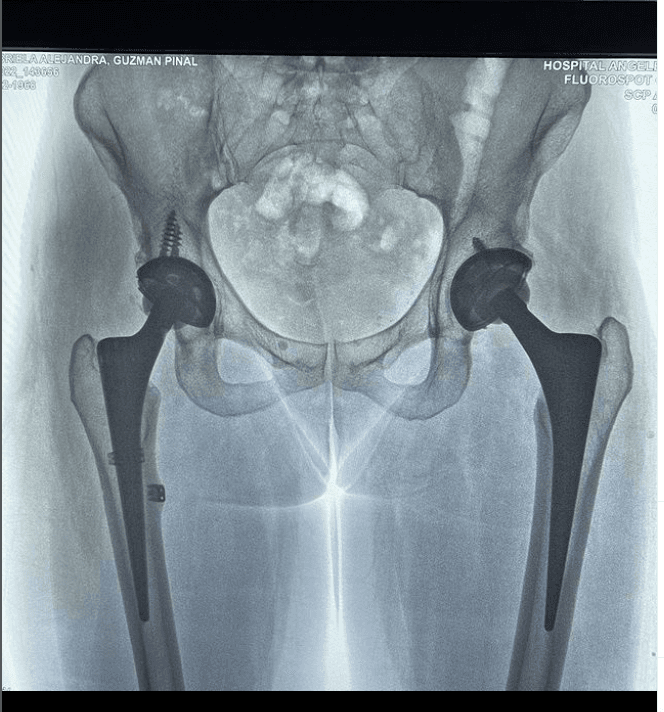

Hace apenas unas horas, la rockera publicó una foto de la radiografía de su cadera que le tomaron en el hospital, sobre la cual colgó un mensaje que se lee "todo en su lugar".

Como puedes ver en la imagen, la hija de Enrique Guzmán y Silvia Pinal tiene una prótesis en cada lado de la cadera que, a su vez, se une con el fémur de cada pierna.